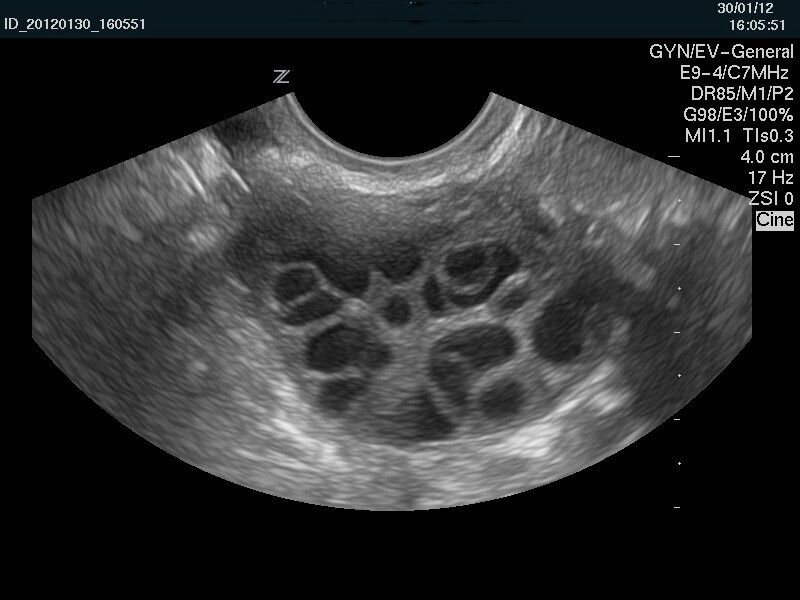

Как лечить поликистоз?

Если вы планируете беременность и на фоне СПКЯ нет овуляции - проводится стимуляция овуляции препаратами Клостилбегит, Фемара, Гонал или Пурегон, никаких других препаратов для стимуляции овуляции не используют. Стимуляция должна осуществлять опытным в этом вопросе доктором, при этом следует обязательно следить за ростом фолликула (фолликулометрия) путем серии УЗИ.